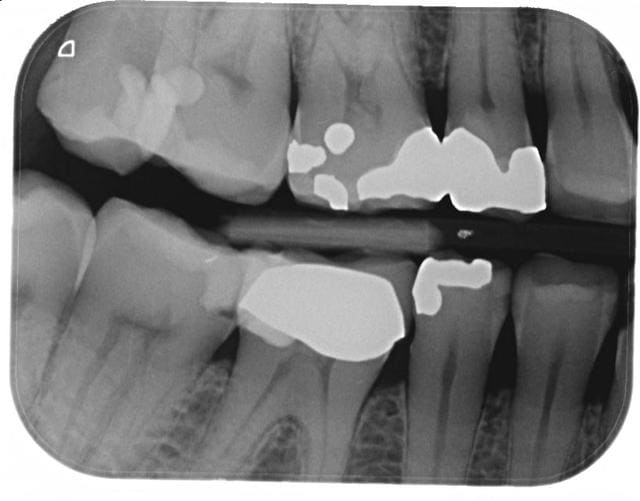

Voici un cas. Patiente 60 ans, RAS anamnèse.

Carie distale sous 47 couronnée et traitée.

Pas de douleurs, aucun signe clinique.

La carie a l'air basse, je ne suis pas sur de la solidité restante des racines après dépose.

Si tu ne fais rien on peut te reprocher une perte de chance d'après la radio la racine a l'aire conservable.

Avec la radio tu es couvert pour déposer la couronne.

Plus bonus si tu dépose la couronne de 47 tu pourras probablement soigner le début de carie en distal de 46 sans déposer la couronne.

Refaire la 47. En profiter pour vérifier la limite distale pas nette de la 46, et probablement refaire 46 dans la foulée.

Et tant qu'à faire s'occuper de la 16, ça évitera de se taper la 17 dans 2 ans.

L'autre côté c'est pareil?

déposer la 47 ne sera pas difficile, vue l'absence de tenon. nettoie bien dessous et recouronner.

La théorie dirait que oui, il y a perte d'étanchéité coronaire depuis longtemps, et la conicité du traitement semble assez faible.